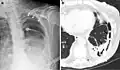

A fibrothorax can typically be diagnosed by taking an appropriate medical history in combination with the use of appropriate imaging techniques such as a plain chest X-ray or CT scan.[3] These imaging techniques can detect fibrothorax and pleural thickening that surround the lungs.[7] The presence of a thickened peel with or without calcification are common features of fibrothorax when imaged.[3] CT scans can more readily differentiate whether pleural thickening is due to extra fat deposition or true pleural thickening than X-rays.[3]

If a fibrothorax is severe, the thickening may restrict the lung on the affected side causing a loss of lung volume.[7] Additionally, the mediastinum may be physically shifted toward the affected side.[3] A reduction in the size of one side of the chest (hemithorax) on an X-ray or CT scan of the chest suggests chronic scarring.[6] Signs of the underlying disease causing the fibrothorax are also occasionally seen on the X-ray.[6] A CT scan may show features similar to those seen on a plain X-ray.[7] Lung function testing typically demonstrates findings consistent with restrictive lung disease.[6]

Extensive left-sided fibrothorax -

Chest radiograph displaying inhomogeneous opacification of the left half of the chest that is fibrothorax -